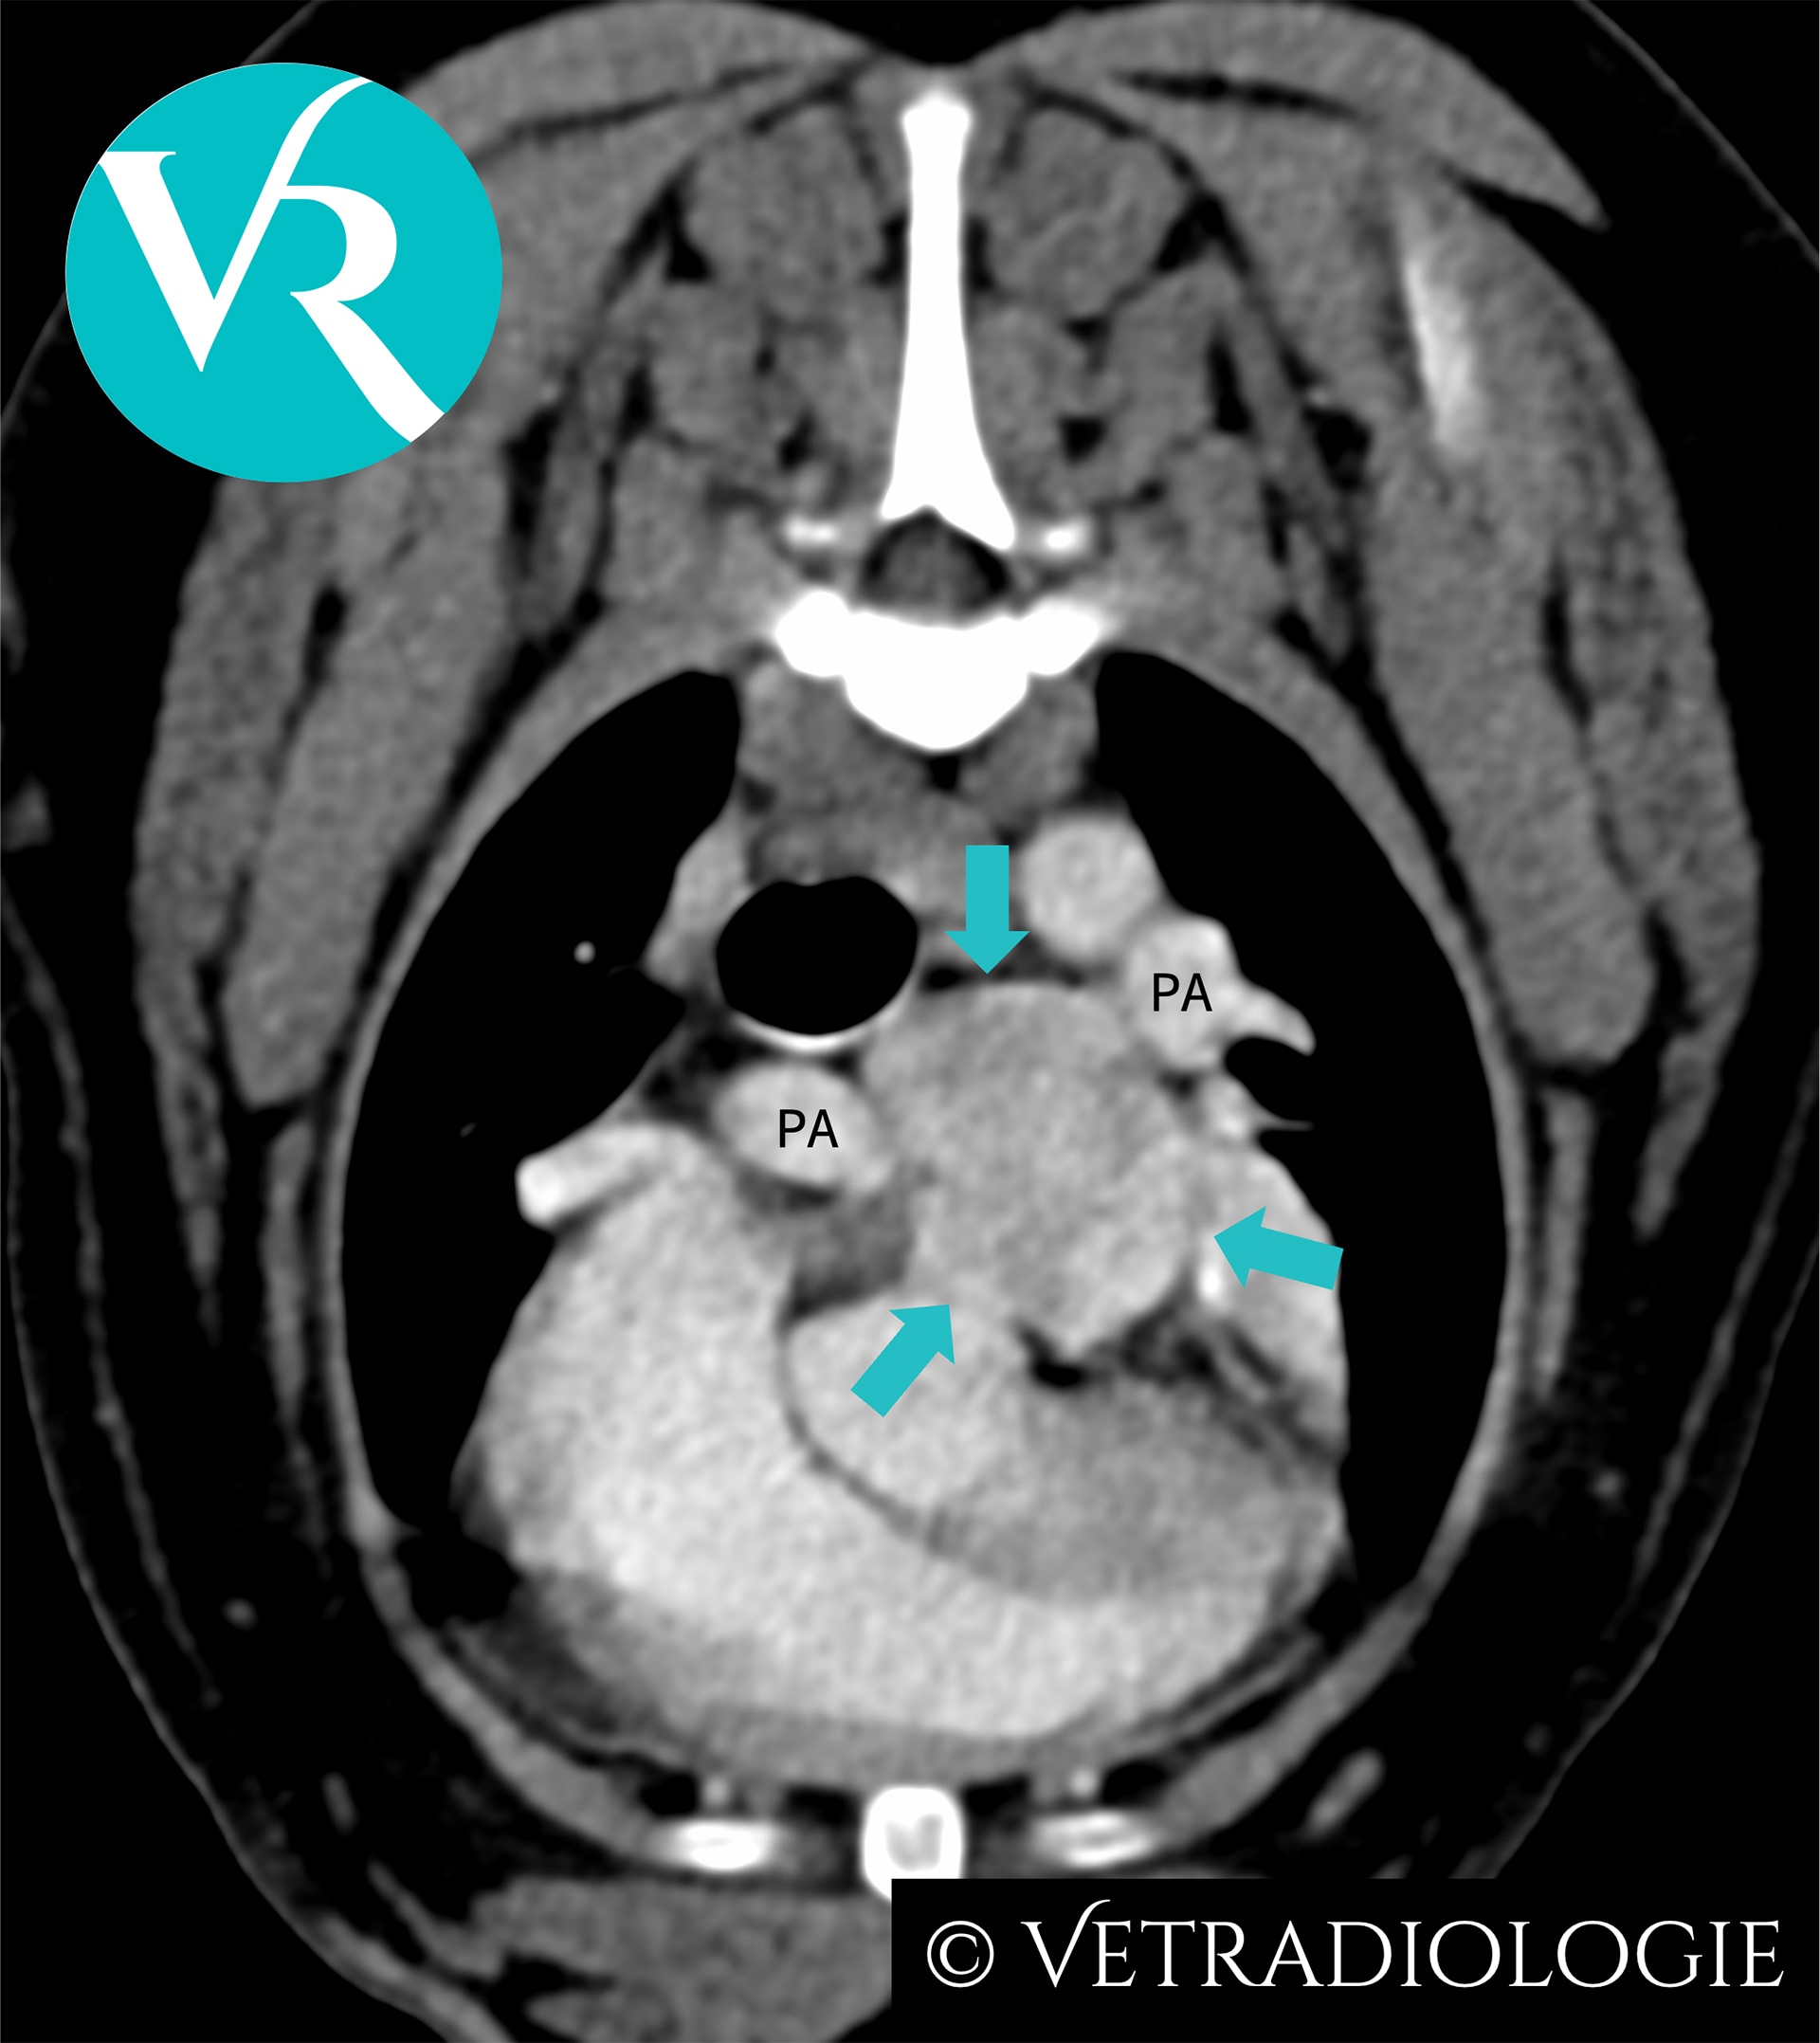

CT-Studie von Mai 2025. Die dargestellte Raumforderung an der Herzbasis war zum Untersuchungszeitpunkt klinisch asymptomatisch.

CT-Untersuchung von Freya: Gut begrenzte, ovoide Raumforderung mit heterogener Kontrastmittelanreicherung (türkise Pfeile) an der Aufzweigung der Pulmonalarterien (PA).

In der CT-Untersuchung von Freya zeigt sich eine umschriebene, hypervaskularisierte Raumforderung an der Aufzweigung der Pulmonalarterien mit heterogener Kontrastmittelanreicherung. Die gut begrenzte, ovoide Raumforderung ist heterogen weichteilattenuiert und im Durchmesser ca. 2,6 cm groß.